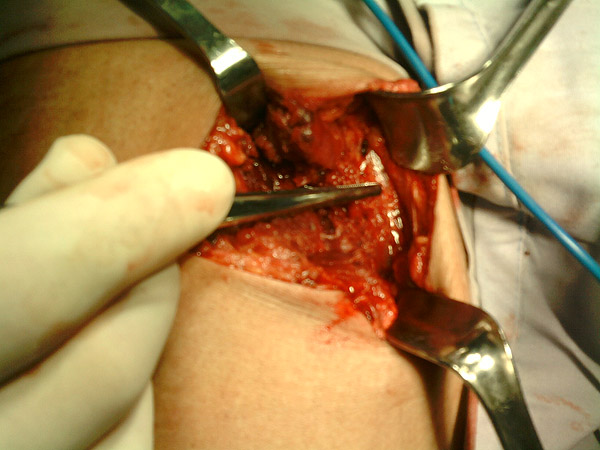

Antes de cerrar la herida